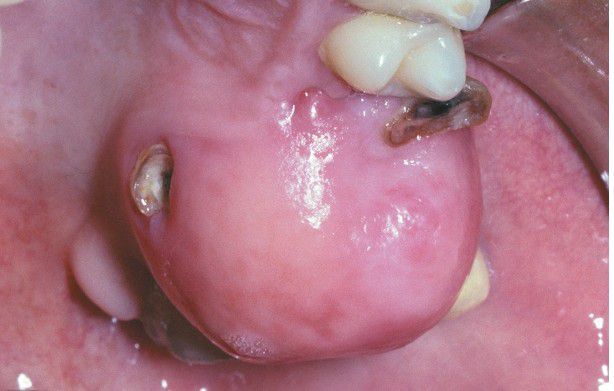

Peripheral Ossifying Fibroma

. Pink, nonulcerated mass arising from the maxillary gingiva. The remaining roots of the first molar are present.